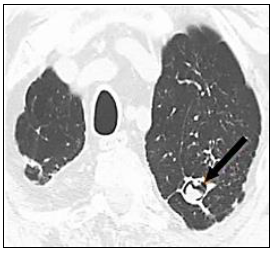

Observe a imagem de TC pulmonar, em que um achado foi marcado por uma seta:

A imagem anterior refere-se a